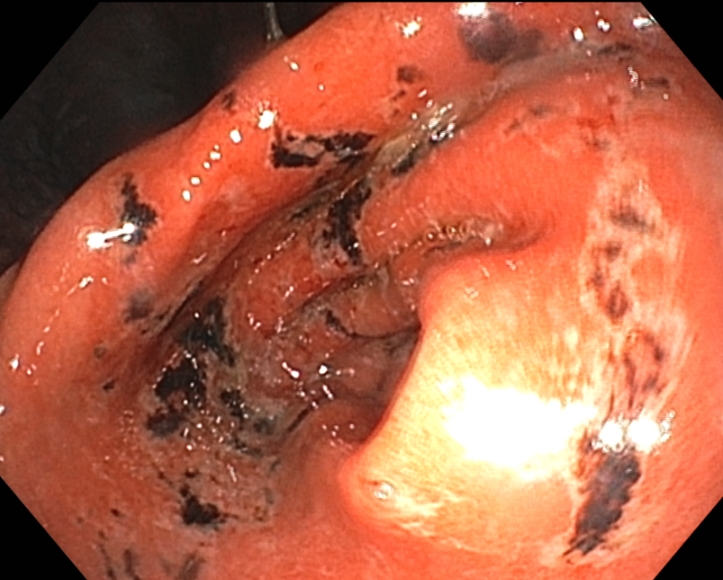

다음은 위내시경에서 확인된 위분문부와 유문부 점막에 생긴 급성위점막병변 사진입니다.